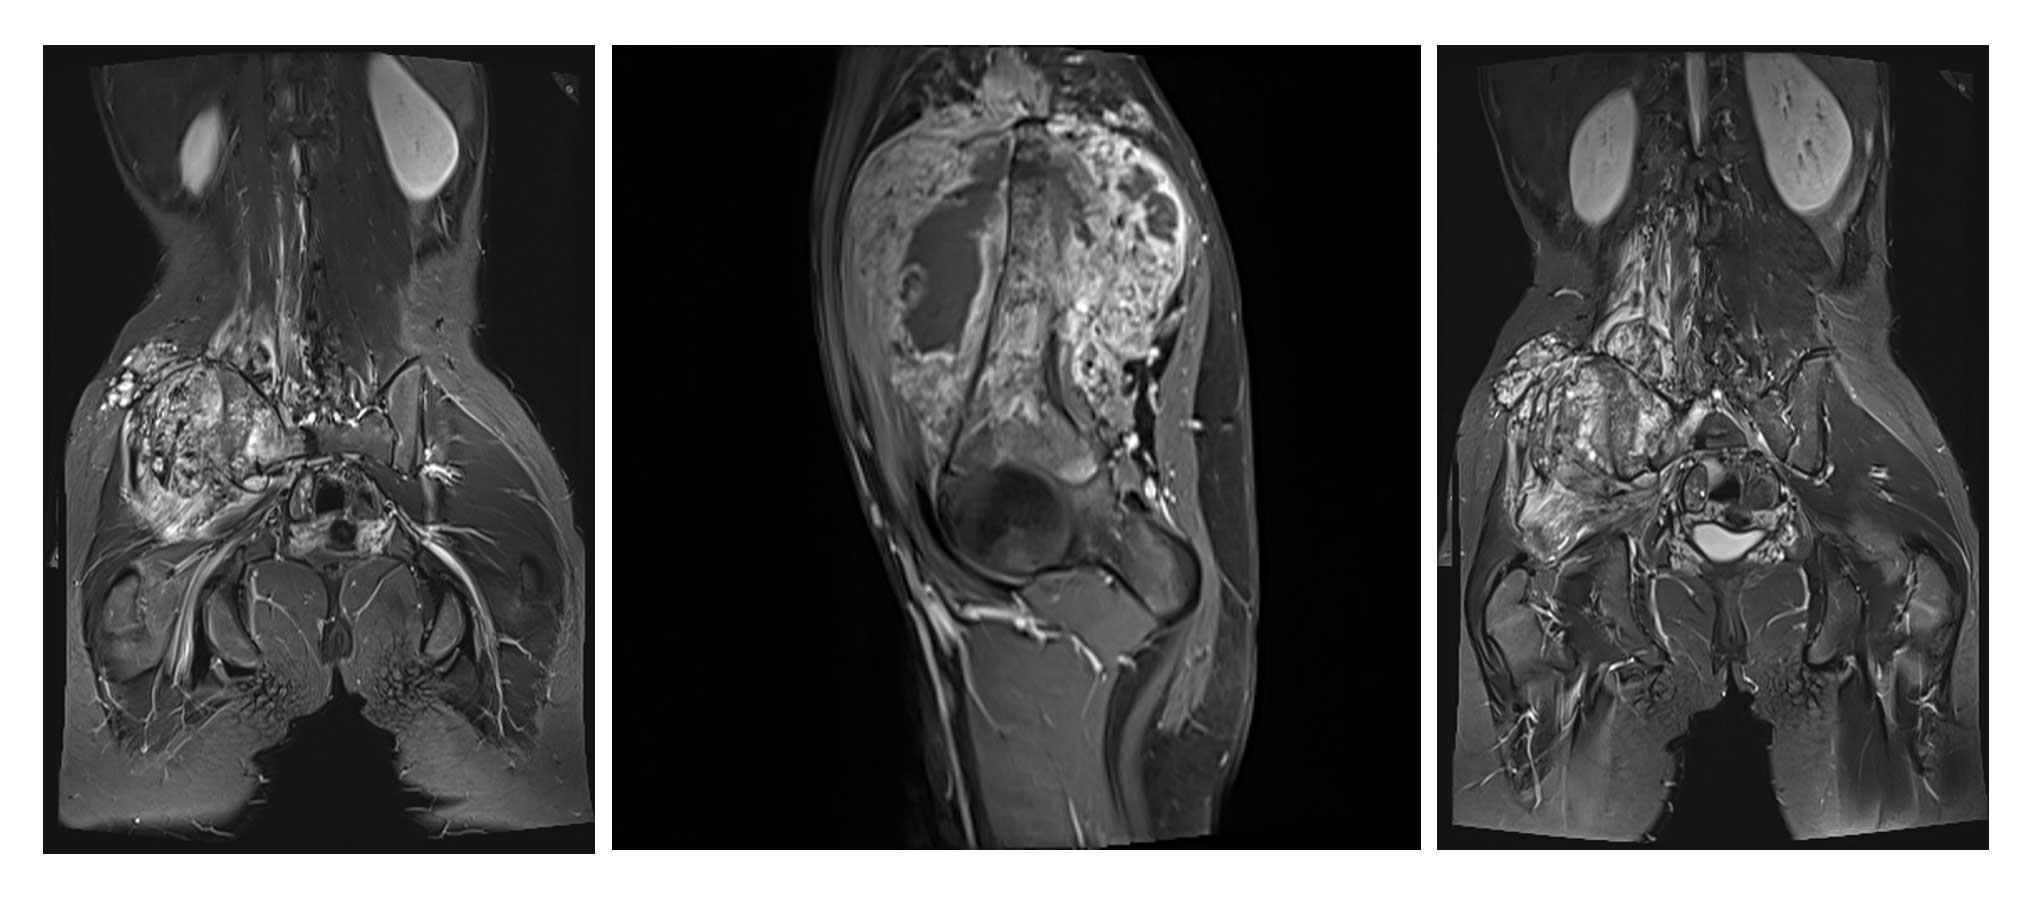

Ameliyat Öncesi: MR’da lomber 4.vertebradan başlayıp sakrum ve iliak kanattan kalça eklemine kadar uzanan yumuşak dokuyu infiltre eden ve kemik harabiyetine neden olan tümör dokusu görülmekte.

Ameliyat Öncesi: MR’da lomber 4.vertebradan başlayıp sakrum ve iliak kanattan kalça eklemine kadar uzanan yumuşak dokuyu infiltre eden ve kemik harabiyetine neden olan tümör dokusu görülmekte